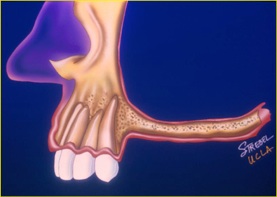

インプラントは歯茎の中の骨がないと植立できません。そのため、その骨が足りない場合が一番、インプラントをする上で問題となります。下顎では過下顎神経管という太い神経が顎の骨の中に通っていますので歯茎からその神経が近い場合骨移植が必要となります。また、上顎では太い神経はありませんが、副鼻腔という大きな空洞が顎の中にありますので、歯茎から副鼻腔が近い場合も骨移植が必要となります。